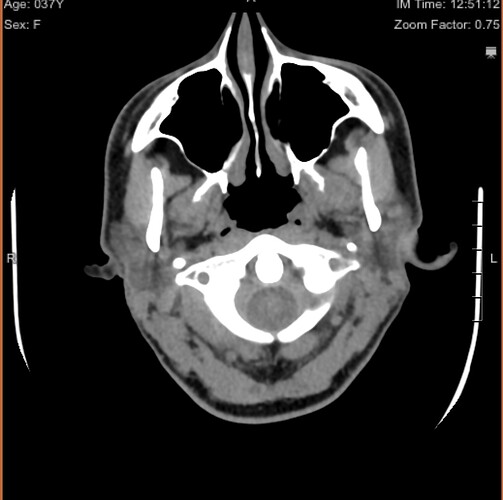

@SeekingInfo there should be a series of images called “axial”, but sometimes it’s called something else. What we want to see is the axial view of C1. I’ve uploaded my own to help you know what to look for. It’s the top vertebrae with a white circle in the top middle:

Hi- I think I may have found what you were asking for. Thanks again for your time, it’s beyond appreciated.

Hi @SeekingInfo yes they are the ones. Both your Styloids are extremely close to your C1 transverse process. I would assume therefore that you will have vascular compression probably IJV. Hopefully other members will give you their opinions shortly.

@SeekingInfo this is perfect, see attached annotated image.

Your styloids are extremely close to your C1, practically touching. This is important because the IJVs and vagus nerves (and also spinal accessory nerve) run between the styloids and IJV.

Research shows that the average space between a styloid and C1 in a healthy individual is about 9mm. I’d be surprised if you have more than 1.5mm between your styloids and C1.

I would recommend getting both styloids removed and to make 100% sure that whichever surgeon you decide to go with cuts the styloids above the level of C1. If they do not cut them above C1 you are going to continue to experience IJV compression symptoms.